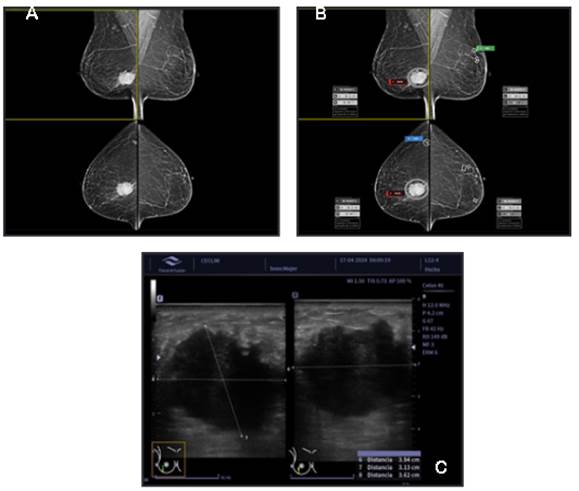

A pesar del potencial prometedor de los algoritmos de IA en la evaluación de las mamografías, también existen algunas limitaciones y desafíos que deben abordarse. Uno de los desafíos clave es la necesidad base de datos de conjuntos voluminosos, diversos y bien incluidos para entrenar y validar estos algoritmos.10 Otro desafío es la necesidad de una evaluación y validación rigurosa de estos algoritmos en entornos clínicos del mundo real y ensayos clínicos prospectivos para garantizar su seguridad, eficacia y generalización6. Aparte de todos estos algoritmos de aprendizaje profundo para la evaluación de la mamografía, en este momento falta información sobre la historia personal o familiar de los pacientes y la información de otras modalidades de imágenes como la ecografía, la mamografía con contraste o la resonancia magnética y su correlación con las muestras de patología. Aún necesitamos más tiempo para llegar al “mejor momento” de los algoritmos de IA (Figura 3). Mientras escribimos este artículo de revisión, se están desarrollando asistentes médicos artificiales para abordar estas limitaciones que acabamos de señalar, pero aún no para un uso clínico generalizado.

Figura 3 A. Paciente de 43 años con una masa palpable en su mama derecha. No es evidente por Mamografía Digital. 3.B. No identificada por algoritmo de IA. 3.C. En la ecografía una masa sólida irregular altamente sospechosa. 3.D. En la Mamografía con Contraste la imagen recombinada resalta una masa en su polo inferior (hipercaptante). 3.E. Carcinoma ductal infiltrante en la biopsia con aguja gruesa. Centro Clínico de la Mama - CECLIM, Caracas - Venezuela. Work station for mammography, DIARM DM™ and brAInray™, Artificial Inteligence for Mammography, USA, 2024, http://www.medicalscientific.com/